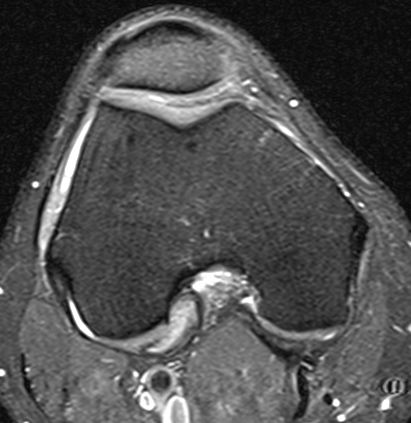

Diffuse

Diffuse PVNS with involvement of suprapatella pouch and posterior compartments, including posterior extra-articular